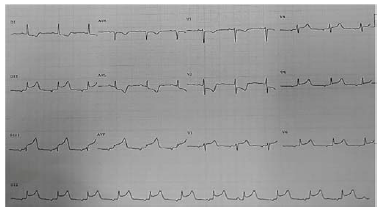

Um paciente de 55 anos de idade chega ao pronto-socorro com dor torácica há três horas, dispneia e sensação de sufocamento. Ao exame físico, apresentava-se em Killip III. Foi solicitado eletrocardiograma, demonstrado na imagem.